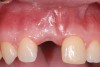

Fig 11. Age 20. Extraction sites with intact labial plates. Their vertical height was near the level of the proximal bone of the adjacent teeth.

Figure 11

After that the patient was seen in the endodontic office periodically to monitor the retained roots and associated alveolar ridge. The root of No. 8 was retained for 8 years after fracturing, and the root of No. 9 was retained for 9 years. During that time there were no clinical signs or symptoms, nor were there radiographic signs of periradicular breakdown. A final endodontic check at age 19 found the coronal surface of the root of No. 9 had been exposed. The vertical level and horizontal width of the alveolar ridge appeared very similar relative to the adjacent teeth as it had been at ages 10 and 15 (Figure 8 and Figure 9). No evidence of periradicular breakdown appeared radiographically (Figure 10). The patient's growth was deemed nearly completed and he was referred to an oral surgeon for evaluation and placement of implants.

At age 20, an oral surgeon placed implants in the Nos. 8 and 9 sites. A full-thickness flap was reflected and the roots were extracted.  Both sockets were intact with thin-medium width labial plates (Figure 11). Implants were placed into the sockets, healing abutments were secured, and the flaps were sutured. Four months later the implants were uncovered and restorations were completed. (Author's note: A radiograph of the implants with healing abutments at placement was unavailable for this article.)

Allowing for differences in radiographic angulation, the apices of the retained roots remained in a similar position relative to the apices of the adjacent teeth as did the coronal edges of the root relative to the CEJs of those teeth (Figure 3, Figure 7, and Figure 10). It appears that the retained roots preserved the developing ridge associated with them in a manner similar to the developing ridge next to the injury site during the child's 11 years of growth. The final result was an intact alveolar ridge with an adequate labial plate at the proper level for an implant (Figure 11).